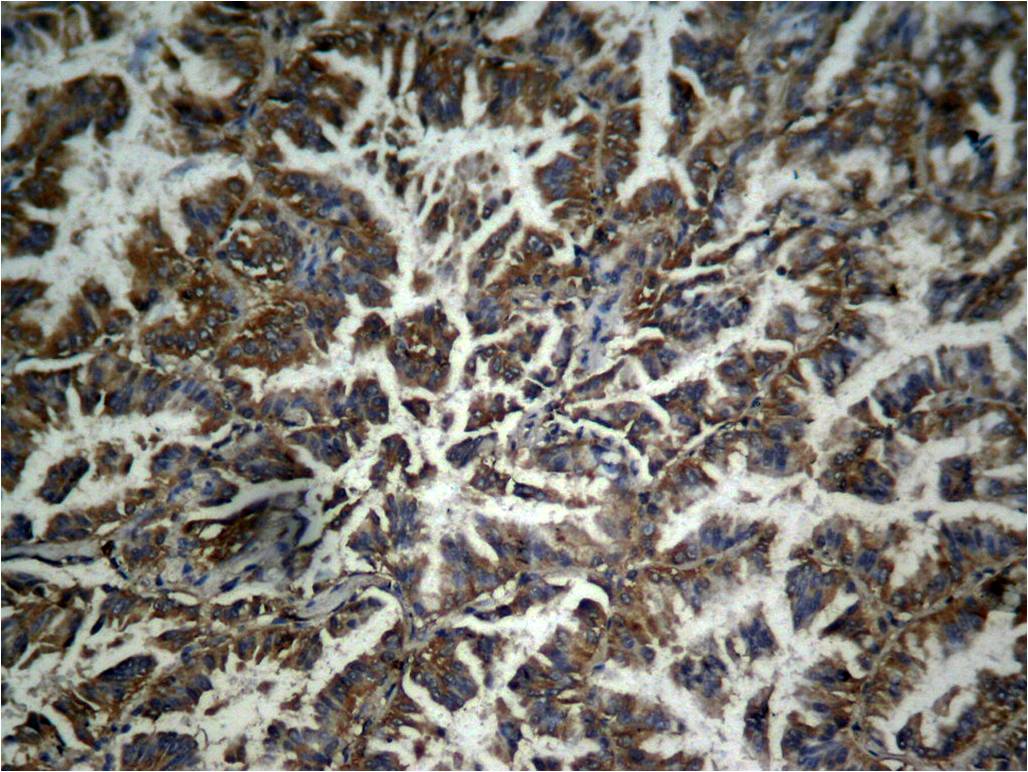

Immunohistochemical analysis of paraffin-embedded human lung carcinoma tissue, using β-catenin (phospho-Tyr333) Antibody#11574.